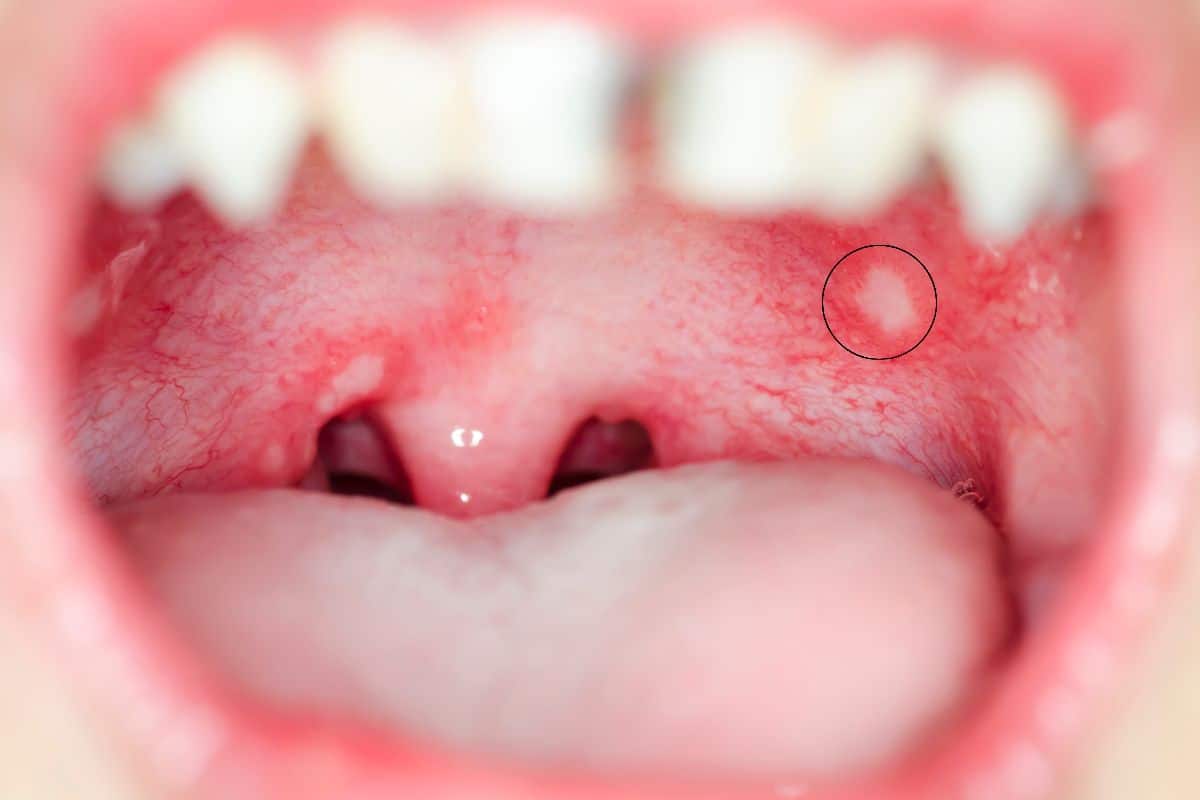

Canker sores are small, round, painful ulcers that appear inside the mouth, including on the roof. They have a white or yellow center with a red border.

They are not contagious. About 20% of people get them regularly. Common triggers include stress, hormonal changes, minor injuries, vitamin deficiencies, and certain foods.

Most canker sores heal on their own within 10 to 14 days. Over-the-counter gels and saltwater rinses can ease the pain in the meantime.

Roof of Mouth Hurts and Has a Bump

A bump on the palate can be a canker sore, cold sore blister, oral thrush patch, or a torus palatinus. Most bumps are benign, but any lump that does not resolve within two weeks should be examined by a dentist.